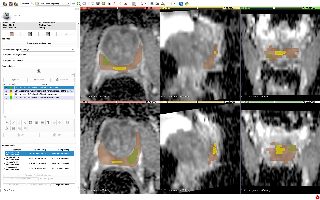

Lung-PET-CT-Dx

| 名称 | 标注内容 | 类型 | 模态 | 数量 | 标签格式 | 文件格式 |

|---|---|---|---|---|---|---|

| Lung-PET-CT-Dx | 肺癌 | 目标检测 | CT | 363 | xml | dcm |